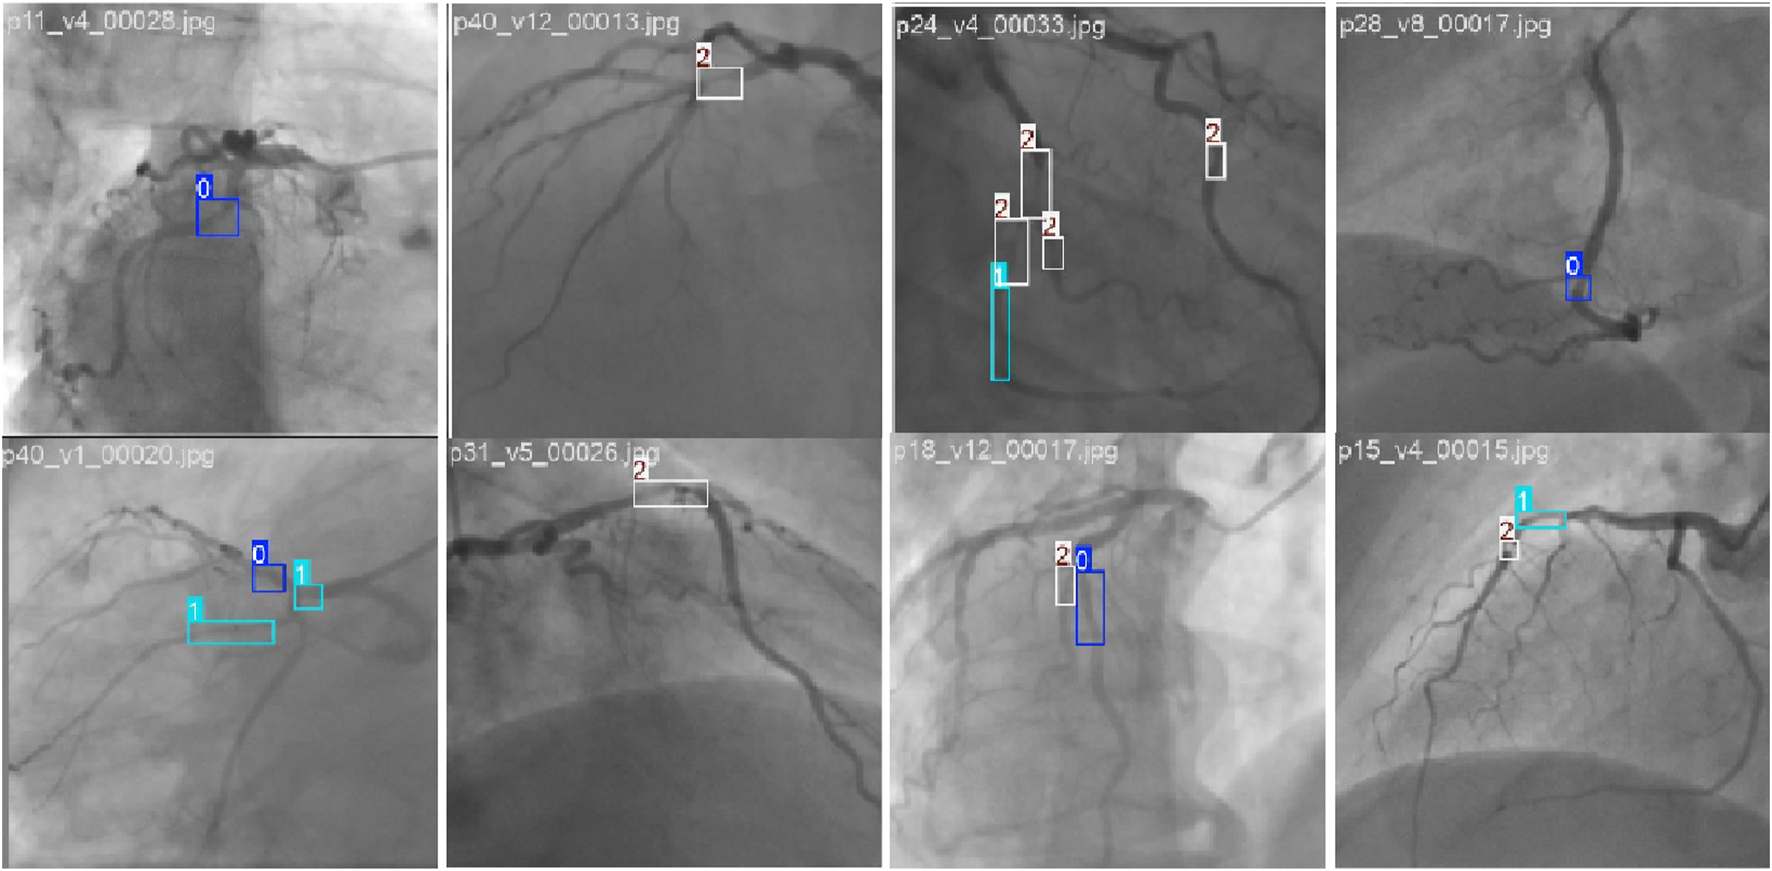

FIGURE 5

Example of stenosis detection and assessment images in the CADICA dataset. The 0, 1, and 2 denote the p0-50, p50-70, and p70-100 stenoses, respectively.

4.3 Visualization results

Figure 11 illustrates the visualization results of LT-YOLO and YOLOv8. The four rows denote the four examples of the prediction results. In each row, the four columns denote the original image, the ground truth, the prediction result of YOLOv8, and the prediction result of LT-YOLO. The first row shows that LT-YOLO is able to locate the stenosis more accurately than YOLOv8. The second row and the last row indicate that LT-YOLO can recognize stenosis that is ignored by YOLOv8. The third row shows that LT-YOLO is more confident in stenosis assessment. In conclusion, Figure 11 proves the superior stenosis detection and assessment ability of LT-YOLO.

FIGURE 11

The visualization results of LT-YOLO and YOLOv8. The dark blue boxes denote the ground truth of small stenoses. The light blue boxes denote the ground truth of moderate stenoses. The black boxes denote the ground truth of severe stenoses. The red, red, and white boxes denote the prediction results of small, moderate, and severe stenosis, respectively.